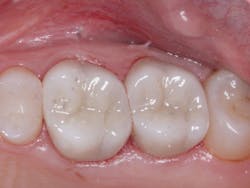

A: Full-zirconia restorations have been available for the past years or so. They have evolved from relatively unesthetic, opaque crowns and bridges to significantly improved restorations with acceptable esthetics (figures 1 and 2). Most dentists have noted that the majority of zirconia restorations are lighter in color than they requested on their lab order. The intense opacity of this material makes the restorations appear light in color. As the new generation of "esthetic zirconia" restorations continues to improve, this color problem will probably be overcome.

Figure 2: Full-zirconia restorations on the first and second molars show the significant improvement in color now available with full-zirconia restorations.